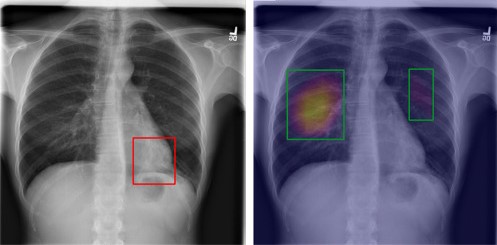

3.3 Bounding Box Generation

We use the Captum library[Kokhlikyan2020] to generate the Grad-CAMs[Selvaraju2019]. We devise Algorithm 1 to generate bounding boxes from Grad-CAMs. The result of Algorithm 1 is shown in Figure 4. We calculate the area of the bounding box from the TBX11k training set images. Then we set the minimum area to ensure that our generated bounding boxes are not too small.

This bounding box generation process represents a core novelty of our work, enabling weakly supervised localization without any explicit bounding box annotations during training. Traditional localization methods demand pixel-level or bounding box labels, which are costly to obtain in medical domains due to the need for expert consensus. By deriving bounding boxes post-hoc from Grad-CAM heatmaps produced by the distilled student model, we leverage the model’s learned attention to infer lesion boundaries accurately. This approach not only bypasses the annotation bottleneck but also scales to large datasets, potentially reducing costs by orders of magnitude in resource-limited settings. The threshold and minimum area filtering ensure that only salient, TB-relevant regions are boxed, further emphasizing disease-specific focus over spurious elements.

We measure our result both quantitatively and qualitatively. The qualitative result is shown in the Figure 5. Each row displays an example of a tuberculosis (TB) chest X-ray image taken from the validation subset of the TBX11k dataset. A detailed inspection of these images reveals a significant difference in how the teacher and student models attend to the visual features. Specifically, the teacher model tends to highlight incorrect or irrelevant areas of the chest, suggesting that it is relying on spurious correlations rather than meaningful disease indicators. In contrast, the heatmaps generated by the student model closely align with the ground truth bounding boxes, clearly indicating that it has successfully learned to identify the key features associated with TB lesions. This comparison demonstrates that the student model is better at focusing on diagnostically relevant regions, reflecting a more accurate and clinically useful understanding of TB pathology.